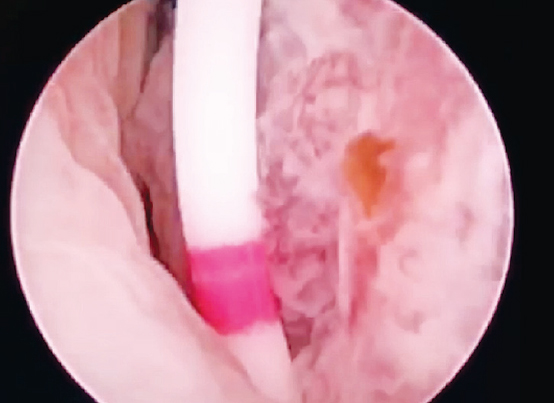

Под эндотрахеальным наркозом после катетеризации ипсилатерального мочеточника в положении пациента на животе под ультразвуковым и рентгенологическим контролем произведена пункция полостной системы правой почки через среднюю группу чашек. Пункционный ход бужирован по гидрофильной струне до 28 Ch и установлен кожух Амплатц. С помощью резектоскопа выполнена ревизия полостной системы правой почки, выявлена мелковорсинчатая опухоль лоханки на ножке (рис. 2). Произведена en-block-резекция стенки лоханки с опухолью при помощи тулиевого волоконного лазера FiberLase U2 (рис. 3).

Рис. 3. Этап резекции стенки лоханки с опухолью с помощью тулиевого лазера единым блоком

Fig. 3. Stage of resection of the pelvis wall with a tumor using a thulium laser in a single block

Используемые параметры лазера для резекции: мощность 1,0 Дж, частота 10 Гц. После en-block-резекции удаленная опухоль извлечена наружу при помощи эндоскопических щипцов (рис. 4).